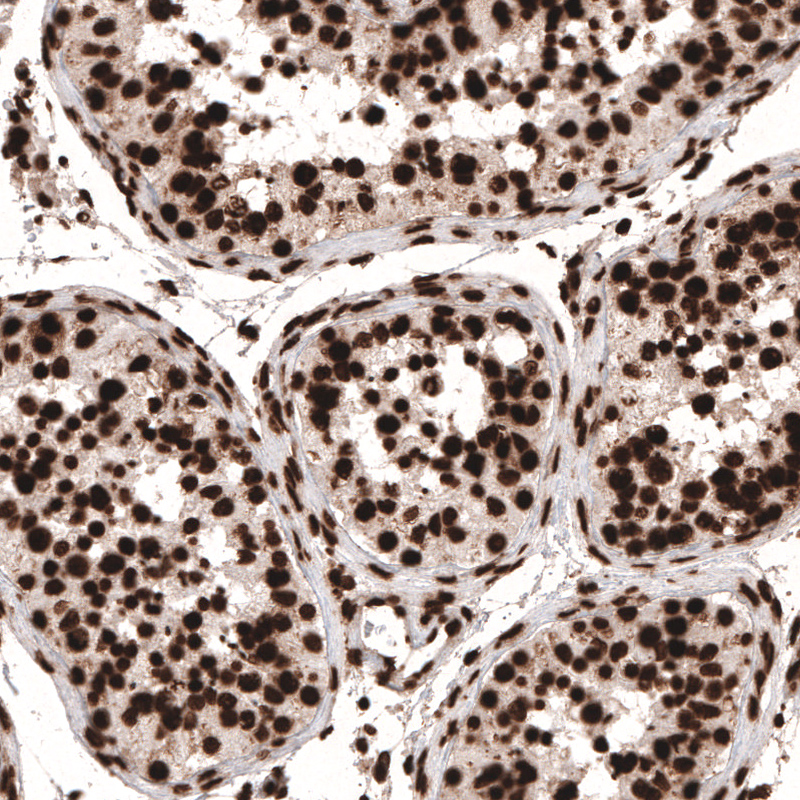

Immunohistochemical staining of human testis shows strong nuclear positivity in cells in seminiferous tubules.